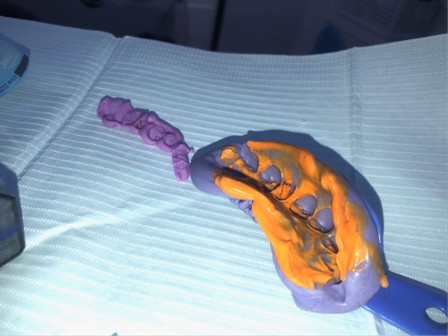

August 1, 2025: Tooth preparation, gingival retraction, shade selection, and impression taking were performed sequentially; the patient tolerated the procedures well